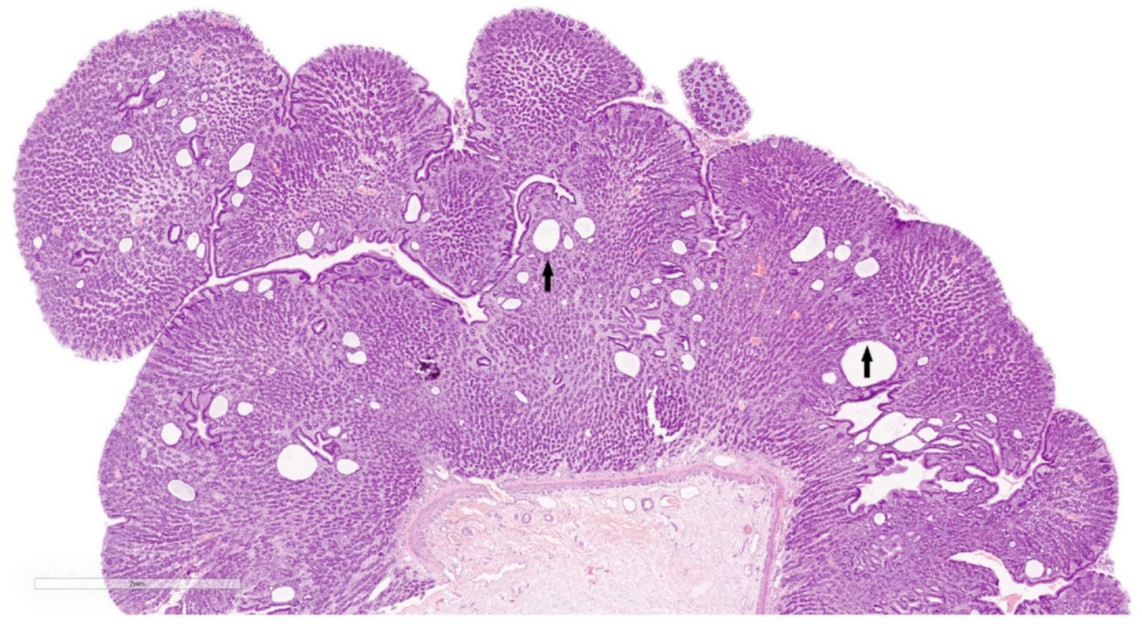

在组织学上,可见黏膜层弥漫性显著增厚。表面柱状上皮多灶性溃疡,但在完整区域无异常。在整个黏膜中,少量大小不一、囊性扩张的黏膜腺体由单层扁平至立方上皮细胞排列(下图)。在少数区域,主细胞轻度增生,壁细胞缺失。

↑ 黏膜层弥漫性显著增厚,可见多灶性囊性扩张的黏膜腺体(箭头)。